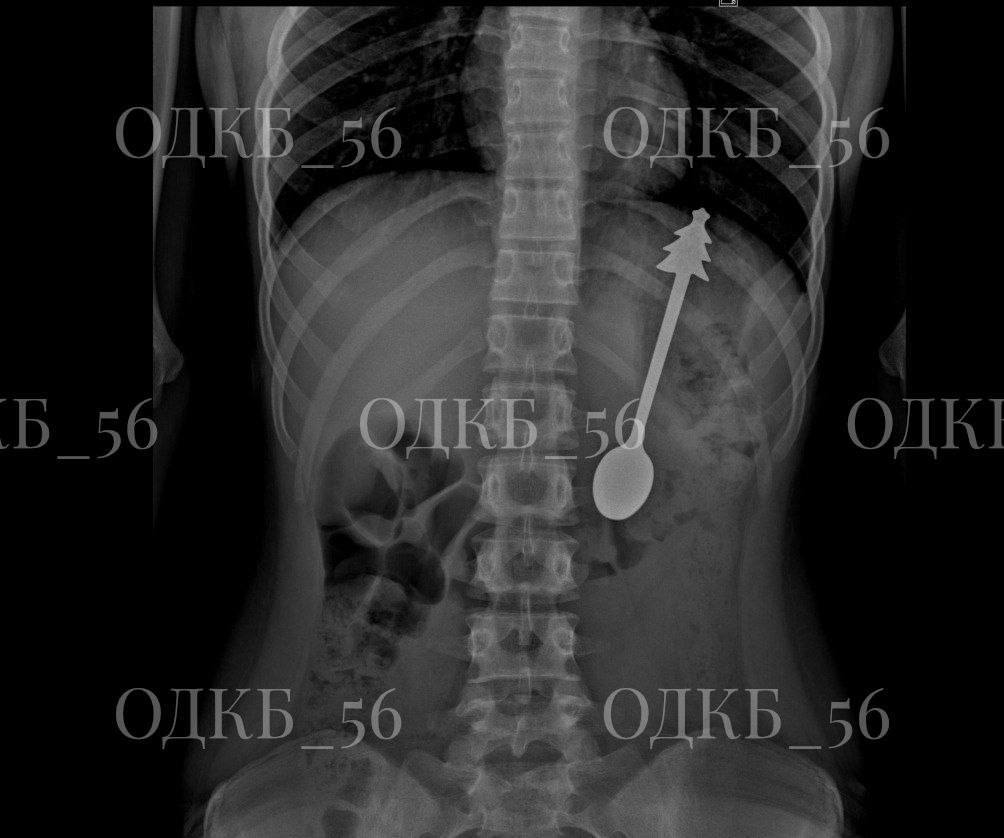

Ребёнок проглотил ложку длиной 14 сантиметров, сообщает Ult.kz со ссылкой на Telegram-канал «Новости из Кремля».

В Москве бригада скорой помощи доставила в больницу ребёнка с жалобой на попадание постороннего предмета в пищеварительные пути. При обследовании было установлено, что ложка застряла в желудке.

В отделении детской хирургии врачи экстренно провели эндоскопическую операцию под общим наркозом без разрезов и извлекли посторонний предмет из желудка.